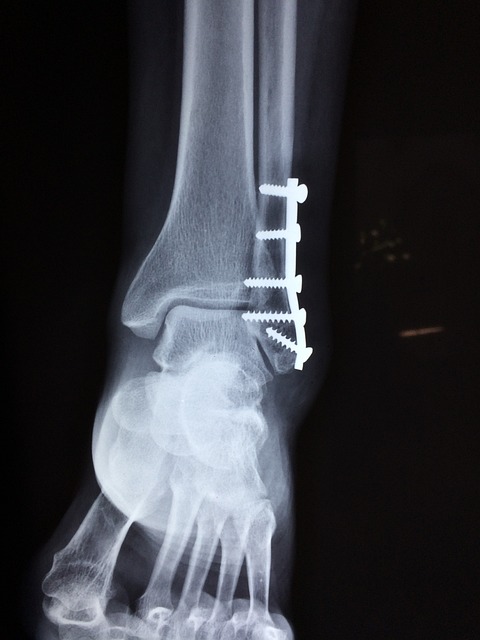

하지만 골절이 발생하면 문제가 커집니다. 골다공증으로 인해 골절이 잘 발생하는 부위는 손목, 척추, 대퇴골입니다. 특히 척추 골절은 증상이 나타나기까지 시간이 걸릴 수 있는데, 키가 작아지거나 등이 구부러지면서 골절을 알게 되는 경우가 많습니다.

골다공증의 치료는 뼈의 밀도를 높이고, 골절을 예방하는 데 목표를 두고 진행됩니다. 치료 방법은 주로 약물 치료, 칼슘과 비타민 D 보충, 운동 등이 있습니다.